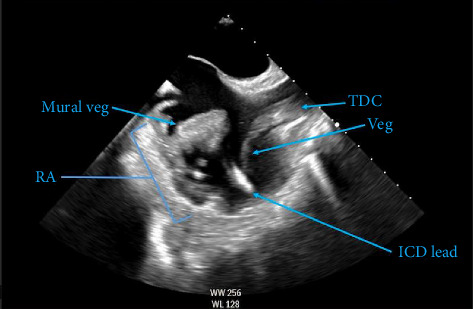

目前的指南不推荐对革兰氏阴性菌血症患者进行常规心脏影像学检查,因为革兰氏阴性感染性心内膜炎是罕见的。引起心内膜炎的非肠道沙门氏菌感染更为罕见,尤其是在发达国家。我们提出的情况下,60岁的女性沙门氏菌血症,最终发现有一个右心房壁心内膜炎涉及植入式心律转复除颤器和留置静脉导管。由于担心经皮穿刺会引起栓塞,我们将植体和留置器移出手术室,并完成了6周的抗生素治疗。治疗完成后,两种留置装置均被更换,在8个月的随访中没有复发的迹象。本病例证明,在心脏植入电子设备和其他进入心脏的留置设备的患者中,如果发现有非典型菌血症,心脏成像作为其检查的一部分可能会受益。

Current guidelines do not recommend routine cardiac imaging in patients with gram-negative bacteremia, as gram-negative infective endocarditis is rare. Nongastrointestinal Salmonella infections causing endocarditis are even more uncommon, especially in the developed world. We present the case of a 60-year-old female with Salmonella bacteremia, ultimately found to have a right atrial mural endocarditis involving an implantable cardioverter-defibrillator and an indwelling venous catheter. The vegetation and indwelling devices were removed from the operating room due to the high concern of embolization if performed percutaneously, and she completed 6 weeks of antibiotic therapy. Both indwelling devices were later replaced once treatment was completed, and there was no evidence of recurrence at the 8-month follow-up. This case proves that in those with cardiac implantable electronic devices and other indwelling devices which enter the heart, who are found to have atypical bacteremia, may benefit from cardiac imaging as a part of their workup.